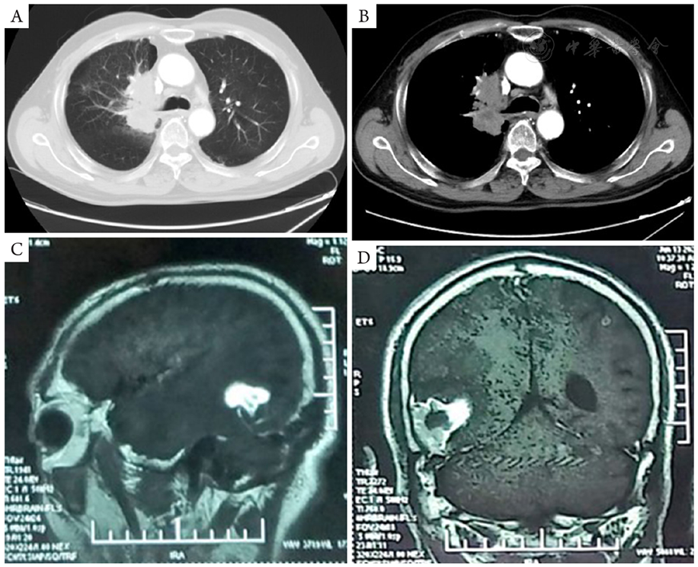

图2 患者单免疫用药治疗1年后外院复查胸部平扫CT及头颅CT情况。A,B:胸部平扫CT右肺上叶及右肺门区病变,最大横截面积约65 mm × 43 mm;C,D:头颅CT示右侧颞枕叶、左侧顶叶病灶(箭头示)较前局限。CT:计算机断层扫描